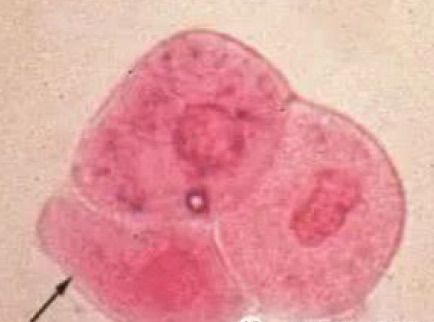

A, :移行上皮细胞